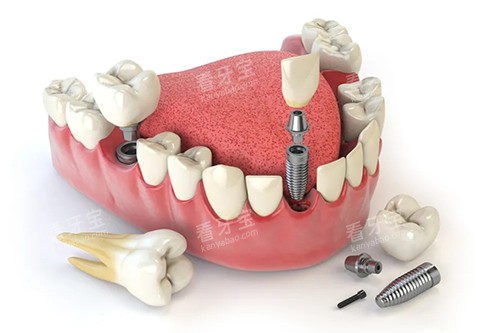

在特色项目方面,哈尔滨鲸鱼口腔的牙齿矫正和种植牙技术尤为突出。

在种植牙方面,医院引进了国内外可靠的种植系统,由经验充足的医生进行操作,确保种植牙的成功概率和稳定性。